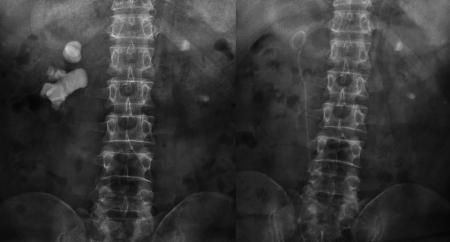

宋先生術(shù)前與第二次術(shù)后的結(jié)石對(duì)比“我兩個(gè)腎臟都長(zhǎng)結(jié)石,到現(xiàn)在已經(jīng)長(zhǎng)了30年了。自從2000年做了開(kāi)刀取石后,前前后后做了100多次體外碎石,結(jié)石還是瘋長(zhǎng)不停。”近日,在四川結(jié)石病醫(yī)院泌尿外科病區(qū),來(lái)自四川沐川縣的宋先生告訴記者,他的腎臟不知怎么回事,每隔個(gè)一兩年就長(zhǎng)出體積駭人的“巨大”結(jié)石。

又進(jìn)行了20多次體外碎石后,腎結(jié)石非但沒(méi)打掉,反而長(zhǎng)到了駭人的8公分:X光片里面形似一顆“老姜”,幾乎塞滿了右腎內(nèi)的大小通道。

“泌尿道梗阻;右腎多發(fā)結(jié)石、中度擴(kuò)張積水;左腎結(jié)石伴左腎積水,左腎縮小。”醫(yī)院的檢查結(jié)果顯示,結(jié)石充滿了宋先生的右腎,右腎功能受結(jié)石和積水的影響,僅剩4成左右,而左腎則出現(xiàn)了可怕的腎萎縮。而這些正是在宋先生接受了驚人的100多次體外沖擊波碎石,累計(jì)花掉20多萬(wàn)元后,付出的沉重代價(jià)。

“人的腎臟約長(zhǎng)10-12厘米,普通人兩、三厘米的結(jié)石,就算比較大的了,而宋先生的腎結(jié)石一年多時(shí)間,就在腎臟內(nèi)迅速長(zhǎng)到8公分。如此驚人的生長(zhǎng)速度,在臨床上十分罕見(jiàn)。”宋先生的主刀專(zhuān)家、四川結(jié)石病醫(yī)院泌尿一科易成然主任介紹。

在經(jīng)歷了兩次微創(chuàng)經(jīng)皮腎鏡碎石取石手術(shù)后,宋先生右腎內(nèi)的巨大結(jié)石被粉碎并清除,解除了尿路的梗阻,腎臟的積水隨之消退。目前,宋先生即將康復(fù)出院。